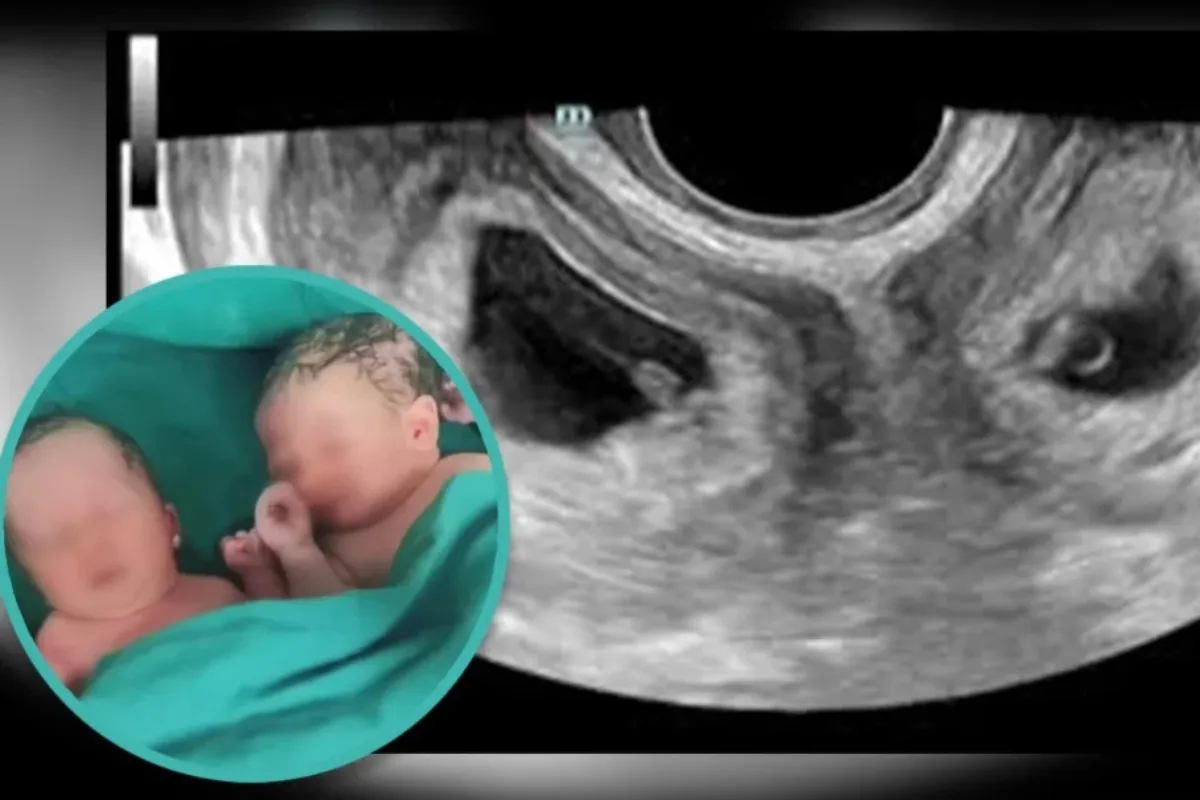

Как пишет South China Morning Post, в сентябре на северо-западе Китая женщина с редким заболеванием — двумя матками — родила близнецов.

По информации больницы, женщина имела две шейки матки и две матки — состояние, известное как удвоение матки, которое встречается примерно у одной из 2000 женщин.

“Крайне редко близнецы зачинаются естественным образом в каждой полости матки, и еще реже их вынашивают”, — сообщили в больнице.

Кстати, мальчик родился с весом 3 кг 300 г., а девочка — 2 кг 500 г.